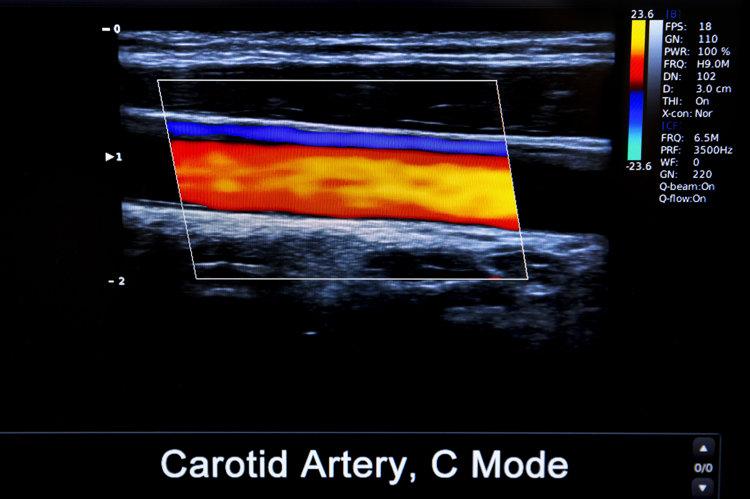

血栓栓塞是由於動/靜脈內形成了血凝塊導致的潛在性致死性疾病。血栓會在血管內隨着血液循環不斷遊離,在任何年齡、任意時間都可能發生,一旦堵塞血管,會導致全身的血液循環系統癱瘓,導致細胞死亡,威脅全身健康。

血栓根據發生部位的不同以及表現可分爲心臟血栓、靜脈血栓和動脈血栓,不同血栓容易堵塞的部位不同。

• 動脈血栓:最容易堵塞心臟,這是十分兇險的病症。一旦凝固的血塊堵住血管,會導致組織器官沒有血液供應,從而誘發心梗、腦梗,沒有及時搶救會導致患者死亡。

• 靜脈血栓:靜脈血栓很容易堵塞肺部,在早期靜脈血栓生成的時候身體可能沒有任何症狀和感覺,但一旦發病就可能會致命。

該症在需要長期臥牀的人身上較爲多見,長期久坐不動會導致體內血液循環變慢,一些血液在深靜脈內不正常凝結會堵塞靜脈期,從而誘發下肢深靜脈血栓。而下肢深靜脈血栓一旦脫落,很可能會引起致命的肺栓塞。

• 心臟血栓:心臟血栓很容易會堵塞腦血管,而心臟血栓容易出現在房顫患者身上。這類患者心房正常的收縮運動會消失,導致心腔內出現血栓。一旦血栓脫落,很可能導致腦血管堵塞,引起腦栓塞。